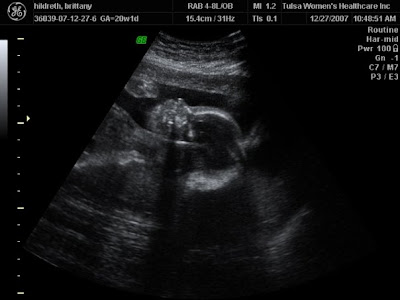

| My first picture of her! 7 weeks long |